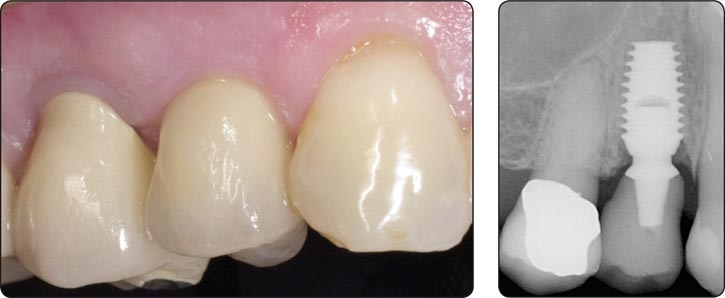

使用Bicon系统很容易获得牙龈美学的修复体-特别是Bicon 一体化基台冠(IAC)的出现。您再也不用因为黑色的龈染线道歉了。